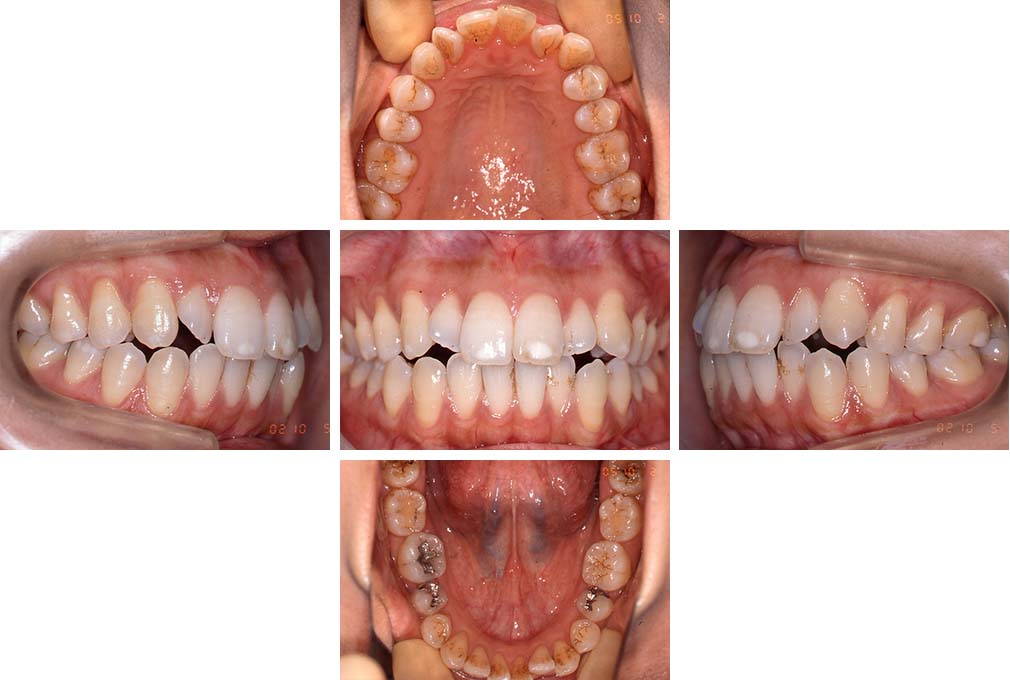

CASE:01

叢生を伴う骨格性上顎前突

初診時年齢 15歳10カ月

性別 男性

治療費の目安 約75万円程度(治療開始時)

上顎前歯の前突と叢生を主訴として来院された。大臼歯関係は左右側ともにⅡ級で上顎の方が前方に位置していた。叢生を伴う骨格性上顎前突と診断し、上下顎小臼歯抜歯を行っていただきマルチブラケット装置に顎外固定装置を併用して動的治療を行った。顎外固定装置や矯正用ゴムの使用など協力状態も良好で、動的治療期間2年0カ月、調整来院20回でマルチブラケット装置を撤去し保定へ移行した。動的治療終了後10年0カ月を経過したが保定移行時とほぼ同様の咬合状態で良好な状態を保っていた。

治療前

15歳10か月

治療後

動的治療期間2年0カ月

18歳5か月

10年経過

動的治療終了後10年0カ月

28歳5か月